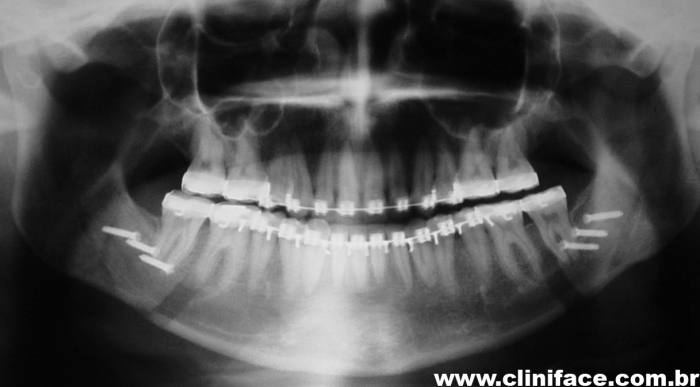

Raio x panorâmico inicial

Raio x panorâmico final